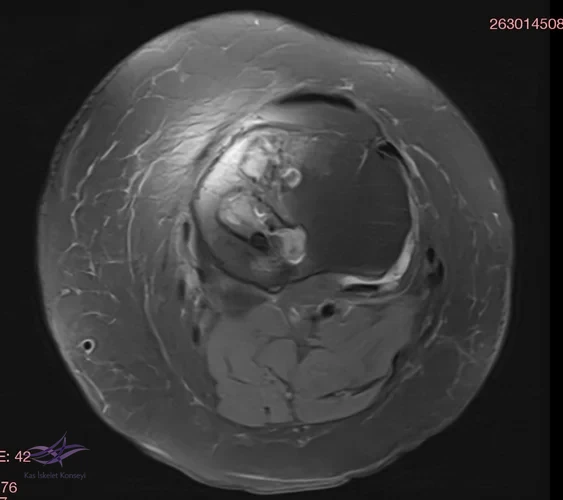

İncelemeler: USG'de minimal suprapatellar efüzyon. MCL heterojen görününde fibrillar yapı bozulmuş. Direkt grafi ve MRG'leri ektedir.

Resim 4. Resim 4. Aksiyal MRG.